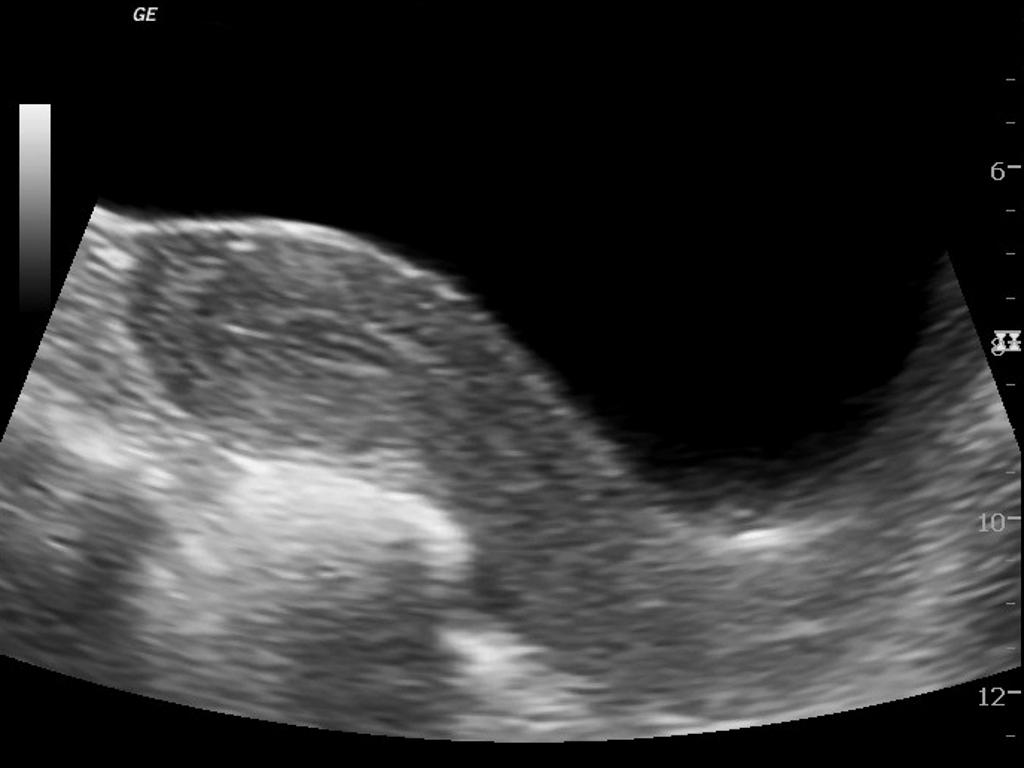

El ultrasonido mamario desempeña un papel crucial en la detección temprana y el diagnóstico preciso de anomalías en los senos, incluido el cáncer de mama. Este procedimiento puede identificar quistes, masas u otros cambios en el tejido mamario que pueden requerir evaluación adicional. Programar regularmente un ultrasonido mamario puede ayudar a mantener la salud mamaria y detectar problemas en etapas tempranas, cuando son más tratables.